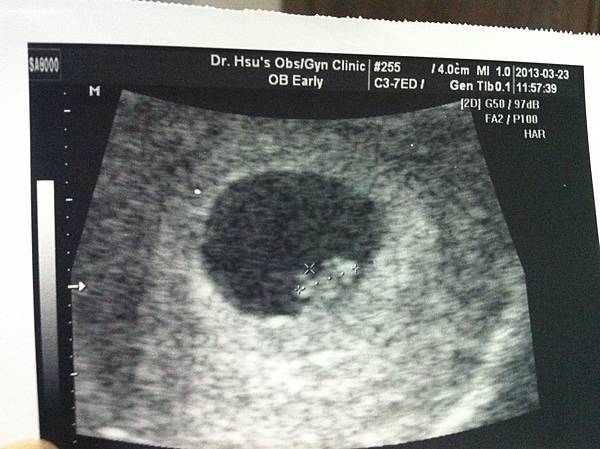

懷孕四個月

肚子有點微凸,但如果不穿的太貼身的話其實還看不太出來,吃東西的口味到現在還沒有什麼明顯的變化,反倒是覺得皮膚變好了,以前很容易長痘痘,但現在反而比較不會長,這是讓我覺得最開心的一件事!所以我跟老公倆都猜應該懷是女娃兒。本想在產檢時確認,誰知道四個月產檢沒有照超音波,只聽了寶寶的心跳,並且看了上次檢查唐氏症及漸凍人的報告。

檢查出來的結果生出唐氏症寶寶的機率是1萬多分之1,簡而言之就是低的,數值要落在270分之1以內才是高危險群,就要再進一步做羊膜穿刺或其他檢查。唐氏症的檢查還有第二期,但我們覺得這樣應該就夠了,就不打算再做第二期的篩檢。

本來我跟老公打算婚後一兩年再考慮生小孩的事,但沒想到計畫趕不上變化,她就這麼來報到了。為了確認我們先找了家裡附近的婦產科做初步檢查,老公知道個訊息還挺高興的,但是我 一 點 都 不 開 心!!!! 躺在婦產科超音波室裡看著螢幕中的胚囊(約5周),我一點喜悅都沒有,醫生搞不好還以為我們是未婚懷孕之類的吧!?剛開始我真的有點崩潰無法接受,因為這完全不在我的預期之中,我還想過一過兩人世界的新婚生活,還想自由自在想去哪玩就去哪玩,有了小孩責任變重了,好像整個原本的世界都要毀滅了,我完全沒有這個心理準備!! 頭一個禮拜我很難以接受,想著想著就會默默流淚,常常在睡前要大哭一場,嚇的老公原本要出國去員工旅遊也不敢去,留在台灣陪我,深怕回來之後會2個人變1個人。